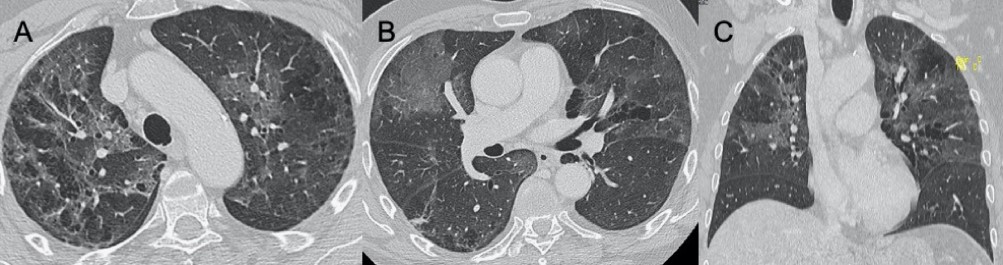

?EB病毒

● CXR:淋巴結(jié)腫大,雙肺間質(zhì)實(shí)質(zhì)受累。

● CT:淋巴結(jié)腫大和較少見的間質(zhì)浸潤伴彌漫性GGO和實(shí)變。

圖9 EB病毒性肺炎。圖(A,C)顯示縱隔淋巴結(jié)腫大(箭頭),與雙肺局灶性小葉GGO相關(guān)(B,D)。